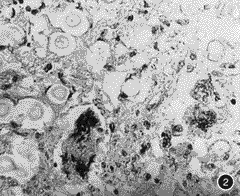

新型隐球菌性脑膜脑炎五例临床病理报告

新型隐球菌病主要侵犯中枢神经系统,如不及时诊治预后很差,现将我院剖检病理证实的五列报告如下。